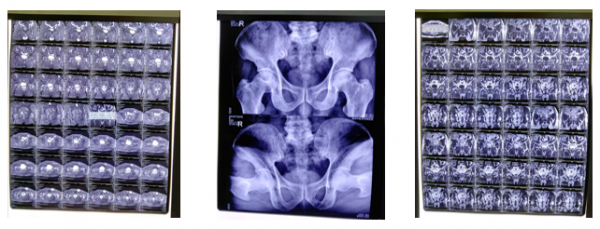

03:典型病例见证